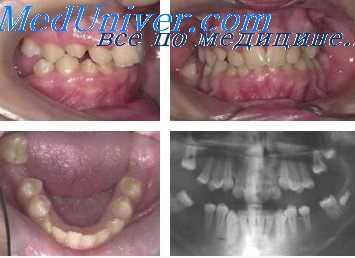

Пациентка Т. А., 16 лет. Диагноз: СЗЧЛА. Мезиальный правосторонний перекрестный буккальный прикус.

Учитывая хорошую форму зубных рядов, отсутствие выраженной скученности, торто-аномалий, лечение начато с установки дуги Cu-Ni-Ti (0,17x0,25). Уже через два месяца достигнута конгруэнтность зубных рядов, сопоставляющихся в конструктивном соотношении со множественными окклюзионными контактами.

В отличие от предыдущих случаев, у данной пациентки хирургический этап включал операцию только на нижней челюсти. В ходе операции мобилизованный срединный фрагмент перемещался кзади. При этом объем перемещения слева был вдвое больше, чем справа. По сравнению с вышеописанными случаями, у данной пациентки были самые неудачные условия и самый неблагоприятный, с точки зрения риска развития рецидива, прогноз. Проведение операции на нижней челюсти при мезиальном прикусе является самым спорным решением с позиций долговременной стабильности результата. Следуя такой логике, давление языка в условиях уменьшившегося объема полости рта должно привести к возникновению рецидива аномалии, особенно при «недостаточно надежной стабилизации» зубных рядов.

Тем не менее мы сочли возможным проведение операции при установленной в полости рта Cu-Ni-Ti-дуге. У этой пациентки прослежены наиболее отдаленные результаты из выборки пациентов, у которых применялся такой план лечения (3,5 года ретенции). А именно ненадежность достигнутого соотношения челюстей являлась одним из аргументов оппонентов данной методики.

Через 9 месяцев после операции удалены элементы ортодонтического аппарата. Установлены несъемные ретейнеры.

Пропорции лица были нормализованы. Прикус стабилен.